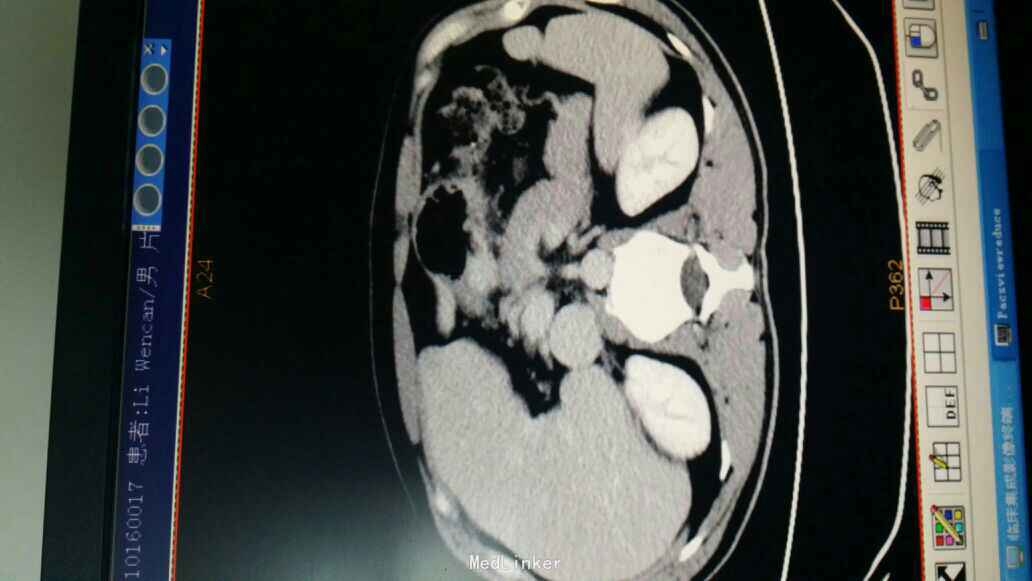

查体:神志尚清,腹部外形腹部外形无异常,腹壁柔软,全腹无压痛,无反跳痛,肝脏肋下未触及,脾肋下未触及,未触及腹部包块,移动性浊音-,肠鸣音正常。脊柱、四肢:无脊柱畸形,无双下肢浮肿,四肢肌张力正常,左侧肢体肌力 Ⅴ级,右侧肢体肌力 Ⅴ级。神经系统:生理反射存在,病理反射未引出。未见其余特殊查体发现。 辅查:血常规:白细胞 5.1 *10^9/L ,血红蛋白 126 g/L ,中性细胞百分比 77.4 % ↑。肿瘤标记物:甲胎蛋白(AFP) 1.41 ng/mL ,癌胚抗原(CEA) 1.24 ng/mL ,鳞状上皮细胞癌抗原 0.50 ug/L ,糖类抗原(CA125) 7.81 U/mL ,糖类抗原(CA153) 6.06 U/mL ,糖类抗原(CA199) 8.24 U/mL ,神经元特异烯醇化酶 失真 ug/L ,糖类抗原(CA242) 2.57 IU/ml ,糖类抗原(CA50) 5.72 IU/ML 。肝肾功能,凝血未见异常。 上腹部CT:1.肝右叶近膈顶小囊肿。2.胃窦部胃腔充盈不良,胃壁未见明显局限性增厚及异常强化。胃镜报告检查报告:胃窦溃疡性质待定;十二指肠球炎。胃炎病理检查报告:(胃窦):低分化腺癌,部分为印戒细胞癌。(胃体):慢性活动性非萎缩性胃炎。送检组织免疫酶标记结果:CK19(+),CK(+),CEA(+),Ki-67(20%+)。特殊染色结果:AB/PAS(+/+)。

术前诊断:胃恶性肿瘤、胃溃疡(胃体溃疡)、十二指肠炎。 治疗:患者入院后完善相关检查,全麻下行腹腔镜下胃癌根治术(毕1式吻合)。腹腔镜腹腔探查:肠系膜、肝脏、胃、腹壁等无转移性结节,因肿瘤较小,术中胃镜下定位,胃镜提示肿瘤位于胃窦部前壁,大小约0.8cm,未侵犯浆膜外,腔镜下予夹子标记,退出胃镜,留置胃管,行腹腔镜下胃癌根治术。术程顺利,术中出血少,未输血,标本及淋巴结送病理,病人安返。术后予对症治疗,恢复佳。